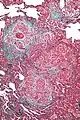

High magnification photomicrograph of a lung biopsy taken showing chronic hypersensitivity pneumonitis (H&E), showing mild thickening of the walls of the small air sacs by invasion of white blood cells. A multinucleated giant cell, seen within the walls of the air sacs to the right of the picture halfway down, is an important clue to the correct diagnosis.

Histopathology

The acute form can be characterized by poorly formed noncaseating interstitial granulomas and mononuclear cell infiltration in a peribronchial distribution with prominent giant cells.[1] The subacute, or intermittent, form produces more well-formed noncaseating granulomas, bronchiolitis with or without organizing pneumonia, and interstitial fibrosis.[1] Much like the pathogenesis of idiopathic pulmonary fibrosis (IPF), chronic HP is related to increased expression of Fas antigen and Fas ligand, leading to increased epithelial apoptosis activation in the alveoli.[21] Cholesterol clefts or asteroid bodies are present within or outside granulomas.[1]

Low magnification view of the histology of chronic hypersensitivity pneumonitis. The interstitium is expanded by a chronic inflammatory infiltrate. Two multinucleated giant cells can be seen within the interstitium at left, and a plug of organizing pneumonia at bottom left.

Lung biopsies can be diagnostic in cases of chronic hypersensitivity pneumonitis, or may help to suggest the diagnosis and trigger or intensify the search for an allergen. The main feature of chronic hypersensitivity pneumonitis on lung biopsies is expansion of the interstitium by lymphocytes accompanied by an occasional multinucleated giant cell or loose granuloma.[7][22]

When fibrosis develops in chronic hypersensitivity pneumonitis, the differential diagnosis in lung biopsies includes the idiopathic interstitial pneumonias.[23] This group of diseases includes usual interstitial pneumonia, non-specific interstitial pneumonia and cryptogenic organizing pneumonia, among others.[7][22]